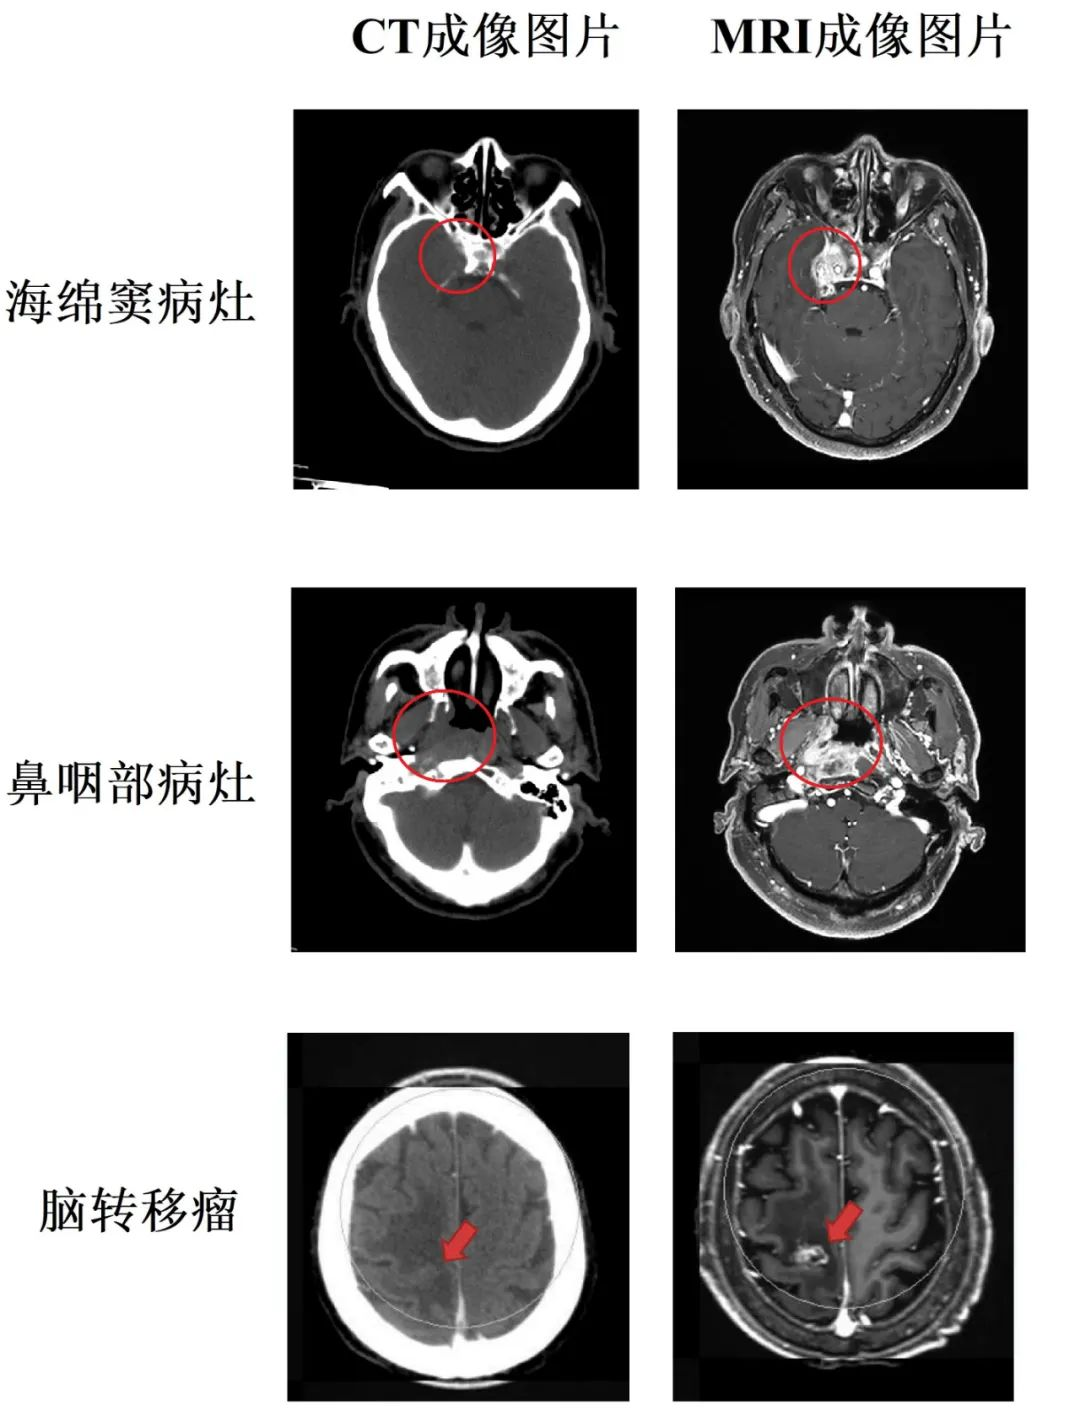

随着精准放疗技术的快速发展,越来越多的肿瘤患者通过放射治疗达到治愈肿瘤、缓解症状、改善生活质量等不同目标。近年来,直线加速器的速度和精度已经达到了一个新高度,要想进一步提高放射治疗的疗效及保护周围的正常组织和器官,影像的质量显得十分重要。传统情况下,头颈部肿瘤放疗前,模拟定位通常采用CT扫描收集图像,然后在CT图像上进行靶区勾画。相对于CT扫描成像,MRI因其成像原理不同,可以获得CT无法达到的优异软组织对比度和解剖成像精度,结合MRI的扫描可以弥补在CT定位扫描中软组织分辨率低的缺点(如下图)。

红标标记为肿物位置

目前,我院在省医放疗科谭佩欣博士积极推动下,肿瘤科袁文金、张敏物理师与放射科李锦华、赖东平技术员等通力配合,突破CT-MRI图像融合的技术壁垒,搭建成熟操作流程。在中枢神经系统肿瘤(胶质瘤、脑转移瘤、颅内生殖细胞瘤)、头颈部部位肿瘤(如鼻咽癌、头颈部鳞癌等)的放疗定位过程中,全部均通过MR与CT图像的融合,利用设备各自的优势,能够更为精准勾画肿瘤和危及器官,可为精确放疗提供更加可靠的图像支持。